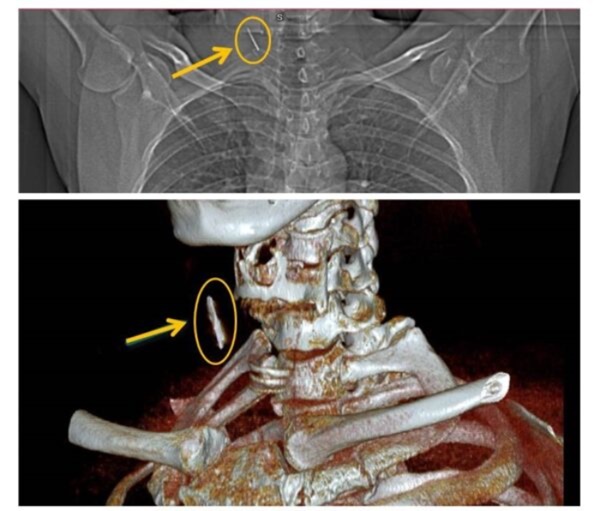

Đi khám sức khỏe tại Bệnh viện đa khoa tỉnh Phú Thọ, anh T.H.C (43 tuổi, trú tại Thụy Vân, Việt Trì) bất ngờ khi được bác sĩ thông báo nghi ngờ có dị vật cắm sâu ở vùng cổ bên phải sau khi xem phim chụp X-quang. Bác sĩ chuyên khoa Tai Mũi Họng đã chỉ định cho bệnh nhân đi chụp CT. Kết quả khẳng định có dị vật phần mềm vùng cổ.

Ngày 24/6, bệnh nhân được phẫu thuật mở cạnh cổ lấy dị vật ra khỏi cơ thể. Dị vật được lấy ra là chiếc đinh kim loại trong trình trạng rỉ sét, được bao bọc bởi tổ chức xơ với kích thước khoảng 2,5 cm. Sau phẫu thuật, tình trạng sức khỏe của bệnh nhân ổn định, dự kiến được xuất viện trong vài ngày tới.

Dị vật trên phim chụp. Ảnh: BSCC.